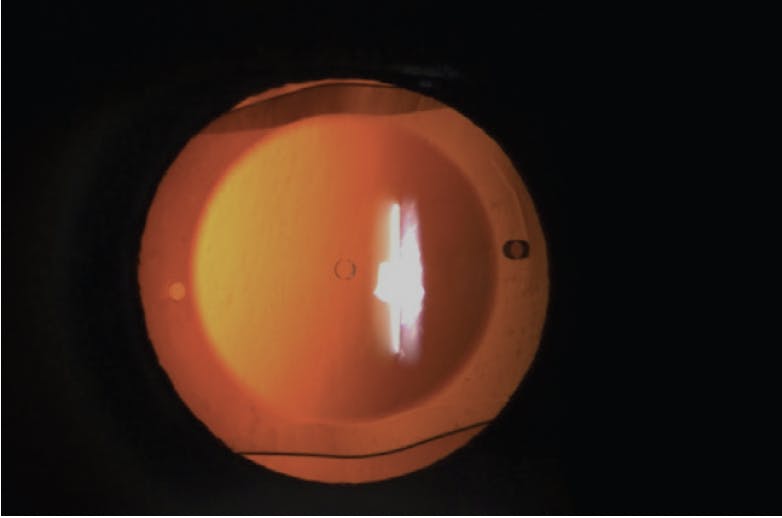

Ingrowth that is peripherally located and that does not affect vision can be simply monitored closely. Once epithelial ingrowth is noted (Figure 2), patients should be monitored every few months initially to ensure it is not progressing.